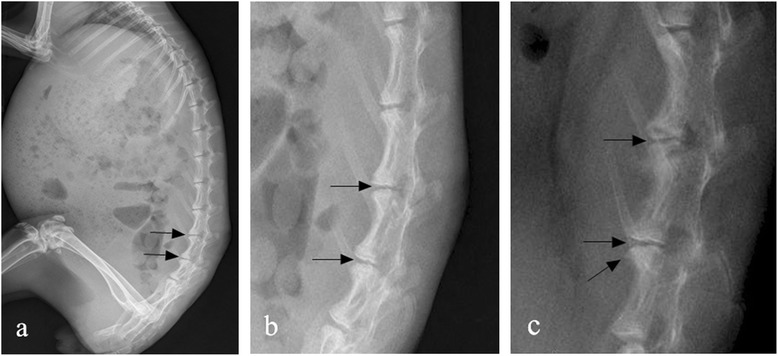

Reduced disk height of L4–5 and L5–6 and early osteophyte formation were shown on lateral radiographs. Endplate thickening (sclerosis) was not observed at any time point (Figure 3).

Figure 3.

Lateral radiographs showing L4–5 and L5–6. (a) Reduced disk height of L4–5 and L5–6 on lateral plain radiographs at 4 weeks after stabbing (black arrows). (b) Neither osteophyte formation nor endplate thickening were observed during this period, only reduced disk height is apparent (original magnification × 2.5). (c) Further loss in disk height was seen at 8 weeks after stabbing (black arrows). Early osteophyte formation (oblique arrow) was observed in this period, but endplate thickening still did not appear (original magnification × 2.0).